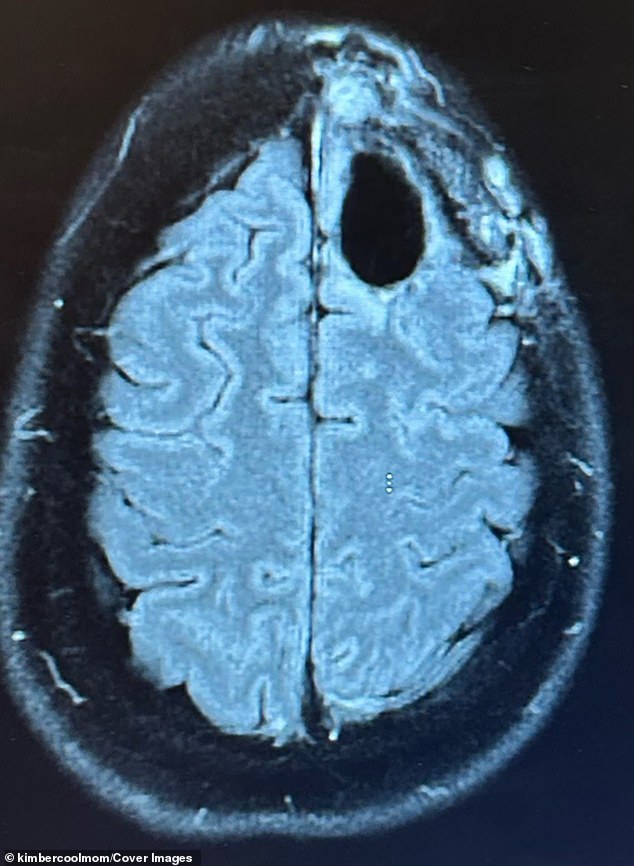

The aggressive, typically incurable tumor [the black patch] was identified in 2022. The cancer attacks the brain’s support cells, often in the frontal lobe, stealing concentration, memory and altering personality

In August 2022, when Pelling went to the emergency department, doctors jumped into action, conducting an MRI that revealed the lime-sized tumor in her frontal lobe.